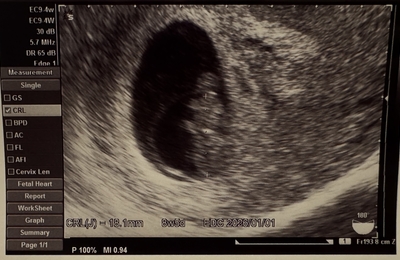

1週間ぶりの病院。 今日も元気にいてくれるかな〜とドキドキ。 つわりは変わらず酷くはないけど、空腹の時が気持ち悪い、、 食べづわりなのかな? 今のブームはきゅうり、トマト、湯豆腐、みかん、りんごです。 いつも通りエコーへ ↓エコー写真 逆立ちしてました!笑 手足が見えてきて、クリオネちゃんみたい。 大きさも順調みたいで一安心です。 次は妊婦健診1回目になるみたい 採血いやだなぁ 9週の壁乗り越える…

都内ゆとりママのびびです。 前回の不妊治療体験記⑥はこちら↓ ①はこちら↓ baby8ee.hatenablog.com 10月の3週でフェニックスアートクリニックを卒業しました。 卒業の日、小さな体に手足が生えているのが確認できました。 感動… サイズも30mmを超えていたので、ネット情報では一安心? 5つ残った胚盤胞は全て保存してもらうことにしました。 ちょうど保管更新の期限が出産予定日周辺に…